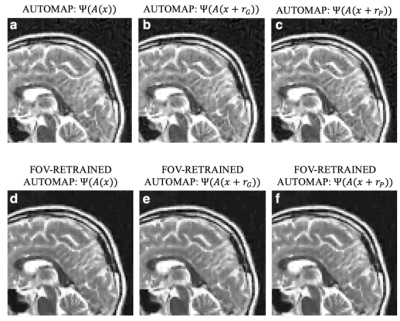

We trained AUTOMAP models to study two properties of training datasets, robustness to FOV artifacts and adversarial noise. The training images were 2D T1-weighted brain MR images acquired at 3 T collected from the MGH-USC Human Connectome Project (HCP) public dataset4. For the FOV experiments, we needed to curate two datasets, one with a single FOV (random samples shown in Fig 1a) and one with multiple FOVs (random samples shown in Fig 1b). Fig 1c was used to showcase artifacts from the different models in Fig 2 and discussed in the results. To study the robustness to adversarial noise and the role of numerical properties of a dataset, the adversarial noise was generated using a gradient ascent with momentum perturbation search algorithm3. The original AUTOMAP was trained to output positive, magnitude images. The adversarial noise pushed this boundary to generate negative and complex-valued noise in the image domain. When applied in the k-space domain, the numerical properties pushed AUTOMAP beyond its reconstruction capabilities leading to artifacts. In Fig 3, we show the adversarial noise is highly structured and contains negative values. Instead of training on positive, magnitude-only images, we added randomized constant offsets (between -0.1 and +0.1) to the training images and retrained AUTOMAP. We show the results of both these models in Fig 4.

The top row in Fig 2 demonstrates what artifacts arise when a model trained on a single FOV is tested on an out-of-distribution FOV in the image domain. All conditions, without noise (Fig 2a), Gaussian noise (Fig 2b), and Poisson noise (Fig 2c), display artifacts (particularly in the dark image background region). After retraining AUTOMAP with multiple FOVs, under both noiseless and noise-applied conditions, the artifacts were significantly reduced (bottom row Fig 2 d-f). We tested and demonstrated how important the role of training data augmentations is through something as simple as incorporating multiple FOVs in the training data. In a clinical setting, these same artifacts could lead to a misdiagnosis or a delay as the clinical practitioners may not be aware where the fault occurred. We also demonstrate the role of the numerical properties of a training dataset and how artifacts introduced by adversarial noise can be avoided. Fig 4a (top row) demonstrates artifacts that arise from adversarial noise. After training a network on images that contain negative offsets due to the adversarial noise consisting of negative values, the retrained AUTOMAP model doesn’t contain the same artifacts in Fig 4b (bottom row). If adversarial noise is a concern, we demonstrate it is important to study the numerical properties of the dataset and augment it appropriately so the model can generalize in practice.

Fig 2: Training data augmentations need to account for multiple fields of view (FOV). We trained two models on two datasets, one built on a single FOV (top row) and one with multiple FOV (bottom row). Under different noise conditions, without noise (a), Gaussian noise (b), and Poisson noise (c), there are artifacts when reconstructing an image with a different FOV than the training data. For AUTOMAP trained with multiple FOVs, the presence of these artifacts is significantly reduced (d-f).